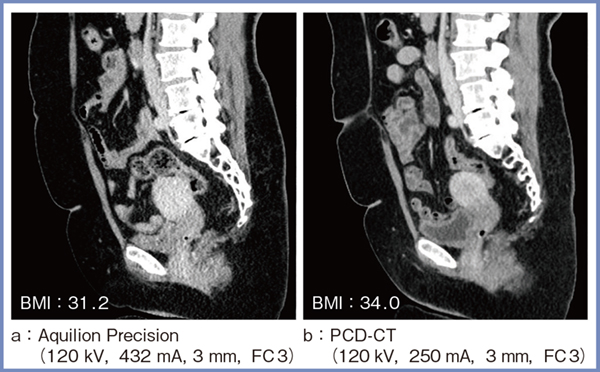

図4は,以前にAquilion Precisionで撮影した症例(a)と,今回PCD-CTで撮影した症例(b)の,腹部骨盤の画像である。いずれもBMI:30以上と肥満傾向があり,Aquilion Precisionでは子宮などでノイズがかなり目立つが,PCD-CTではノイズが非常に少なく,子宮や骨,膀胱などのコントラストも良好である。このように,PCD-CTは,相対的に線量が不足する患者に対しても威力を発揮すると思われる。

図4 相対的に線量が不足する患者の腹部CTにおけるPCD-CTの画質